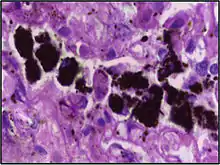

An alveolar macrophage (or dust cell) is a type of macrophage, a professional phagocyte, found in the pulmonary alveoli, near the pneumocytes, but separated from the wall.

Alveolar macrophages are frequently seen to contain granules of exogenous material such as particulate carbon that they have picked up from respiratory surfaces. Such black granules may be especially common in smoker's lungs or long-term city dwellers.